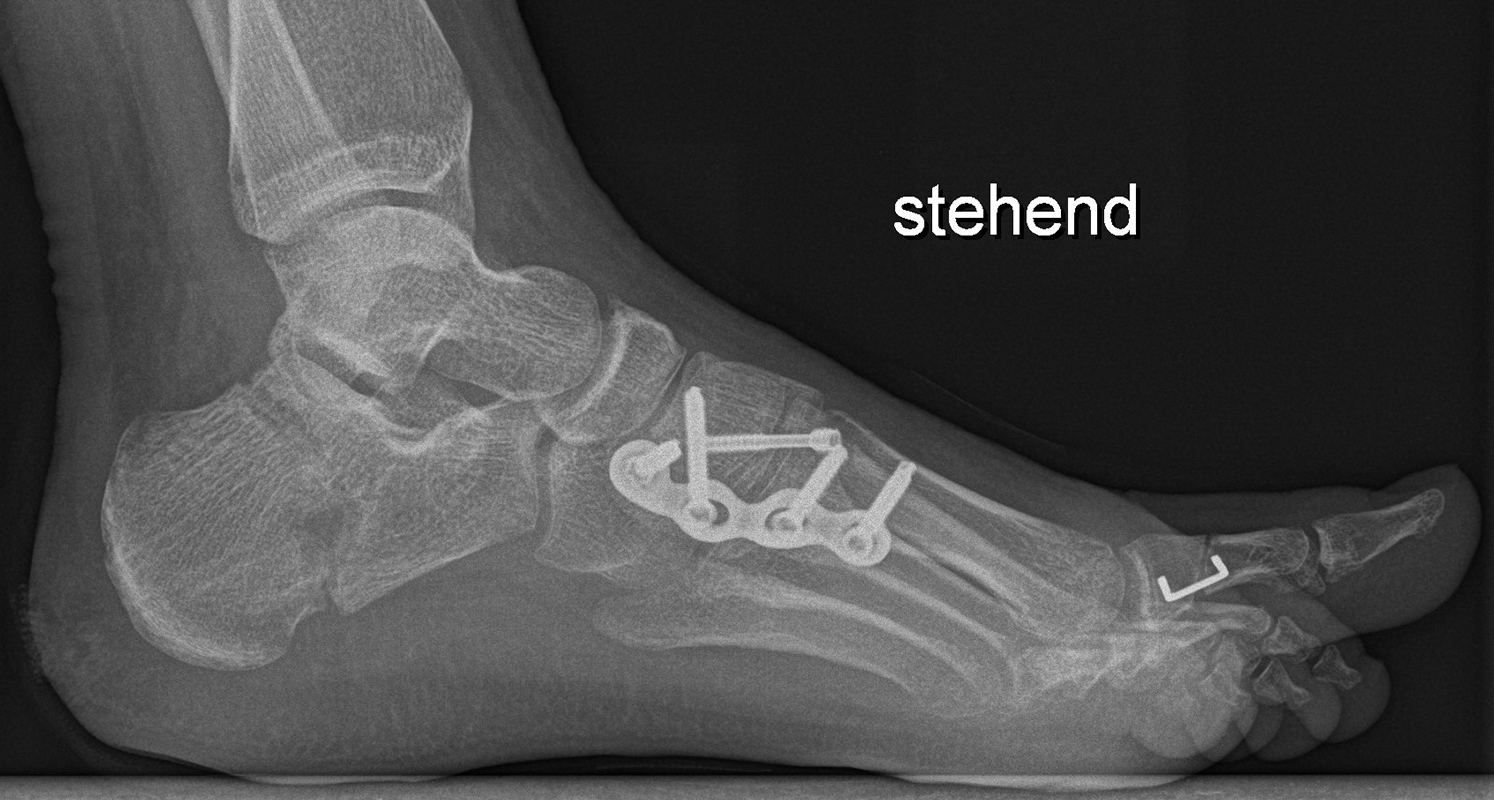

Wachstumslenkung mit moderner Klammer oder eight plate

Bei offenen Wachstumsfugen kann über eine Steuerung des Wachstums mit einer Klammer (Blount-Klammer/Flex Tack) oder kleinen Plättchen (Eight Plate) eine Korrektur von Achsabweichungen in der sagittalen und coronaren Ebene erreicht werden (Abb. 8). Der Hautschnitt beträgt ca. 1,5 - 2 cm und die so versorgten Kinder können ihre Extremität direkt postoperativ schmerzadaptiert voll belasten. Die wachstumslenkende Operation mit einer Klammer oder einem Plättchen besitzt ein enormes Korrekturpotential und erspart dem Kind oder Jugendlichen umfangreiche Umstellungsosteotomien und Plattenosteosynthesen, welche eine Schnittlänge von 15 cm und eine Entlastung des operierten Beines von 4-6 Wochen erforderlich machen.

Abb. 8 a-g: Genua vara prä- und postoperativ versorgt mit Flex Tacks (a-b) und ein Genu valgum versorgt mit Eight Plate an der medialen Femurkondyle (c); Spitzfuß bei congenitalem Klumpfuß und einem Flat Top Talus mit präoperativem Röntgenbild seitlich und der deutlich nach dorsal stehender Tibia(d); intraoperative Bilder der Epiphysiodese mittels Eight Plate zur Wachstumslenkung der distalen Tibia in die Extension (e-f) und postoperativer Verlauf nach sechs Monaten mit regelrecht stehender Tibia über dem Talus durch die distale Extension (g).